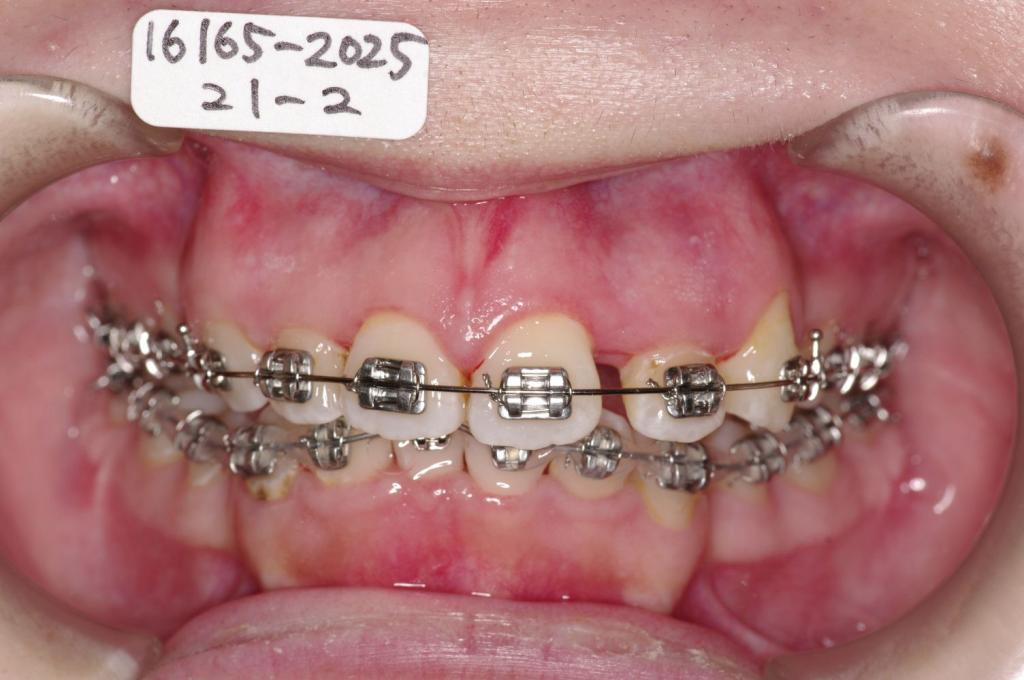

装置の種類及び治療法 診断:叢生

治療方法および装置:マルチブラケット装置

High pull J-hook headgear

抜歯:右上4 /左上4

右下84 /左下48

欠損歯:右上8 /左上8

装置写真

治療前

歯並び・咬み合わせ・八重歯・乱杭歯の矯正治療前口内写真NO.1237